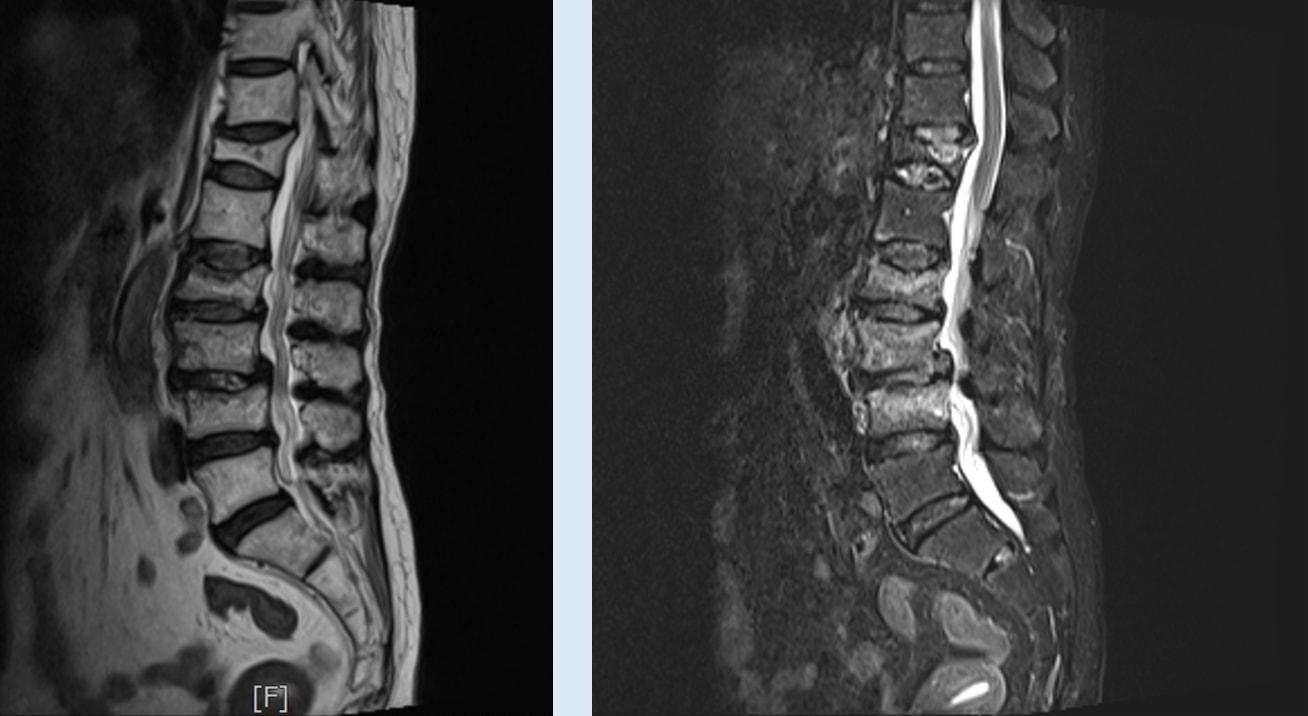

- MRI of Lumbosacral spine Images: T2 and T2 Stir

Findings

- Acute compression fracture of Lumbar spine L2

- Acute bone marrow oedema of Lumbar spine L3, L4 vertebrae

- Old compression fracture of Thoracic spine T12

- After physical examination with MRI, patient was found to have:

- Acute compression fracture of Lumbar spine L2.

- Acute bone marrow oedema of Lumbar spine L3, L4 vertebrae.

- Old compression fracture of Thoracic spine T12.